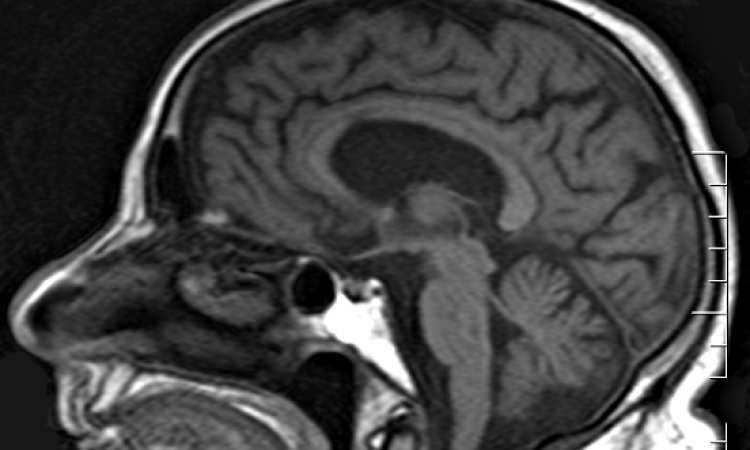

Brain MRI And Dementia Stock Image. Image Of Brain, Sagittal - 105374245

www.dreamstime.com

www.dreamstime.com

mri dementia failure dieting predict loss miethke hydrocephalus sagittal behandlung

Representative Brain MRI Of Dementia Patients. A Patient A Was

www.researchgate.net

www.researchgate.net

dementia mri patients diagnosed publication vascular atrophy